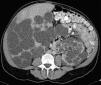

Ultrasonido y tomografía con evidencia de enfermedad poliquistica del adulto. Se realizó fenestración laparoscopica de los quistes hepáticos, con adecuada evolución.

Figura 3. Quistes hepáticos sin complicación.

Figura 4. Enfermedad poliquística renal y hepática.